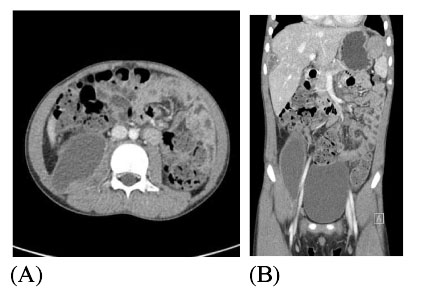

(A). A cross sectional view of the abdominal CT with contrast shows 16 × 4.6 cm sized iliopsoas abscess with enhancing rim on the right side of the abdomen. (B). In an axial view, increased sized multiple intraabdominal abscesses were seen under the subcapsular area of the liver and left subphrenic area.

Fig. 2 (A). A cross sectional view of the abdominal CT with contrast shows 16 × 4.6 cm sized iliopsoas abscess with enhancing rim on the right side of the abdomen. (B). In an axial view, increased sized multiple intraabdominal abscesses were seen under the subcapsular area of the liver and left subphrenic area.